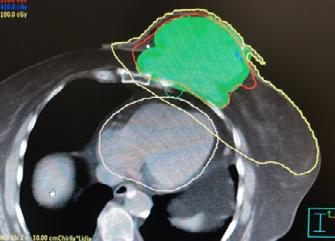

Abstract. Progresele realizate în aplicarea radiațiilor au făcut posibile noi abordări pentru cancerul local avansat. Procesul de „remodelare” este acum o realitate, iar vindecarea locală a tumorii local avansate doar prin radioterapie cu doze mari este acum posibilă. Pe baza tehnicilor moderne de iradiere, cum ar fi IMRT de tip VMAT, Rapid Arc sau Tomoterapie, distribuția dozei conform cu forma volumului tumoral și aplicarea de doze totale mari a făcut posibil procesul de „remodelare” la nivelul țesuturilor moi. Vă prezentăm din propria noastră experiență rezultatul radioterapiei a două tumori mamare local avansate pentru care a fost obținut clinic un control tumoral. Acest lucru a fost posibil datorită aplicării de doze curative de 70 – 72 Gy. În aceste cazuri a fost obținut un control tumoral cu refacerea structurilor invadate. Acest proces de refacere este definit ca „REMODELING“. Etapele vindecării și efectele radioterapiei la nivelul țesutului tumoral și peritumoral (tumor microenvironment – TME) sunt descrise.

Planul de iradiere a pacientei din cazul nr. 2 a fost efectuat la secția de fizică medicală din Centrul de Radioterapie Amethyst din Otopeni.

Planul de iradiere a fost executat după efectuarea unei examinări CT și delimitarea volumelor țintă și optimizarea planului de iradiere, cu aplicarea dozei dorite la nivelul tumorii mamare local avansate cu implicarea tuturor țesuturilor până la rebordul costal.

Evoluția din timpul radioterapiei externe. Înainte de inițierea radioterapiei externe (stânga), cu planul de iradiere aplicat (în mijloc – cu roșu Volumul Țintă iradiat) și după finalizarea radioterapiei. Aplicați au fost 72 Gy.

Evoluția clinică de la începutul radioterapiei și după terminarea ei este redată în figura de mai sus.

Evoluția din timpul radioterapiei externe. Înainte de inițierea radioterapiei externe (stânga), cu planul de iradiere aplicat (în mijloc) și după finalizarea ra-

În literatura de specialitate sunt indicate în cazul tumorilor mamare local avansate regimuri de iradiere cu doze paliative extrem de diferite (10 x 3 Gy, 20 x 2 Gy, 25 x 2 Gy). Noi am aplicat doze curative de 70 -72 Gy.

În concluzie: Progresul în radioterapie este rezultatul îmbunătățirii metodelor imagistice (CT, RMN, PET / CT) și a metodelor realizate în calculul planului de iradiere și de aplicare a iradierii. Tehnicile moderne de radioterapie sunt toate bazate pe intensitatea modulată a fascicolelor (IMRT), ca de exemplu: VMAT (volume modulated arc therapay), Rapid Arc și Tomoterapie. La AMETHYST RADIOTHERAPY CENTER, standardul nostru este administrarea dozei optime la nivelul bolii microscopice (CTV) și macroscopice (GTV) și administrarea unei doze limitate la nivelul organelor cu risc crescut la iradiere, cum a fost în cazul unui cancer mamar local avansat,. Controlul local al tumorii cu efecte secundare acute și tardive reduse fac acum posibilă îmbunătățirea calității vieții acestor pacienți care sigur în alte clinici nu sunt iradiați cu doze locale curative.